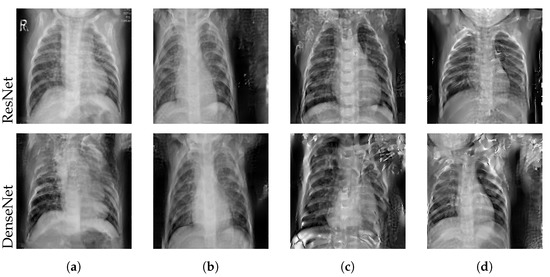

4.2.1. Impact of Layer Freezing

4.2.2. Impact of Training Stage

4.2.3. Impact of Batch Size